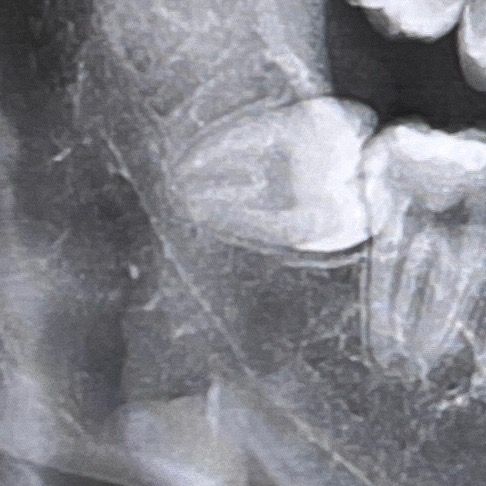

뿌리도 콘처럼 모여서 뾰족하고 유착없이 치주인대강도 잘 보이는데요. CT를 찍어봐야 알겠지만 신경관과 완전히 붙어있지는 않아보입니다. 신경손상의

가능성이 없는 것은 아니지만 큰 무리없이 발치할 수 있을 것으로 보이는데요. 다만 발치라는 것이 아무리 좋은 조건에서 시작한다고 하여도 얘기치 못한 상황이 닥칠수는 있기 때문에 크게 걱정하실 필요는

없지만 발생 가능한 문제점들에 대해서는 어느정도 인지하고 계셔야 하겠습니다.

사랑니가 기울어져 나 있어. 난이도가 높은 발치로 보입니다. 하지만 나이가 어리고 뿌리가 모아져 있기 때문에 나오는데 크게 문제가 되진 않을 것으로 생각됩니다. 자세한 확인을 위해서 치과에서 진료를 받아 오는 것을 권유드립니다.